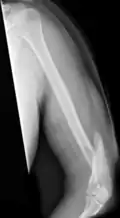

Midshaft humerus fracture with callus formation | |